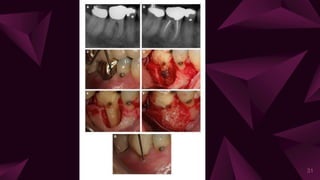

True combined lesions

⩥ It arises when an endodontic disease progressing coronally joins

with an infected periodontal pocket progressing apically.

Characteristics

⩥ Once the pulpal and periodontal lesions coalesce, they may be

clinically indistinguishable.

⩥ Necrotic pulp/ failed endodontic treatment, plaque, calculus and

periodontitis will be present in varying degrees.

Diagnosis

⩥ Probing

⩥ Radiographs

⩥ Pulpal testing: negative.

37

Treatment

⩥ Endodontic therapy

⩥ Periodontal therapy.

⩥ Hemisection

⩥ Bicuspidization

⩥ Root amputation

Prognosis

⩥ Depends on the each individual factor.

⩥ Adequate root canal therapy results in resolution of the

periapical lesion

⩥ Prognosis of the affected tooth then depends totally on the

outcome of periodontal therapy.

38